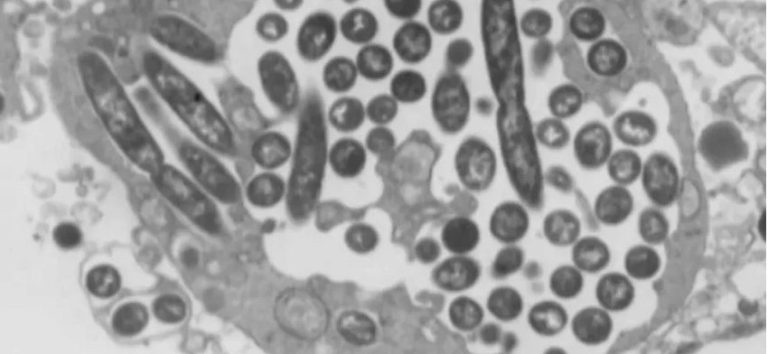

First human case of flesh-eating screwworm parasite detected in the U.S.

The parasite — the larvae of the new world screwworm fly — can devastate cattle herds and is rife in parts of Central America...